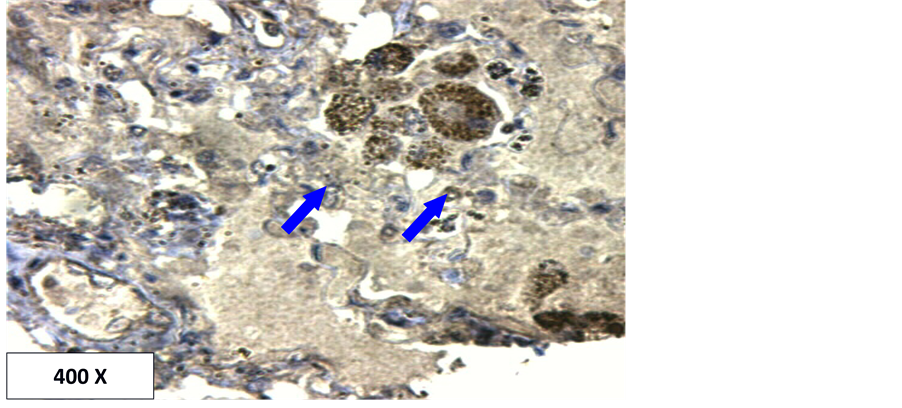

In the current study, the detection of p53 and Aspergillus antigen in lung tissues were investigated using immunohistochemistry technology. The results show that the Aspergillus is present in all used sample (100% of the infection) in the form of spores or hyphae (Table 1, Figures 1-3). It is also present within the blood vessels and within the interstitial spaces (Figure 2 and Figure 3). This high percent may be due to the highly specific and sensitive technique employed in this study (immunohistochemistry). Additionally, all cases in this study were from autopsy specimens, Autopsy specimens are more exposed to Aspergillus than other specimens. There may be relatively long time from death to obtain the specimens which may give a sufficient incubation time for the multiplication of Aspergillus.

When Mach-4 was used as a detection system which is a very highly sensitive detection system, the localization of Aspergillus is clearer even diffused within fluids (Figure 2 and Figure 3). The results show that all

Figure 3. Localization of Aspergillus hyphae in lung tissue using Mach-4 method. Brown color at the tip of the arrows indicates positive.